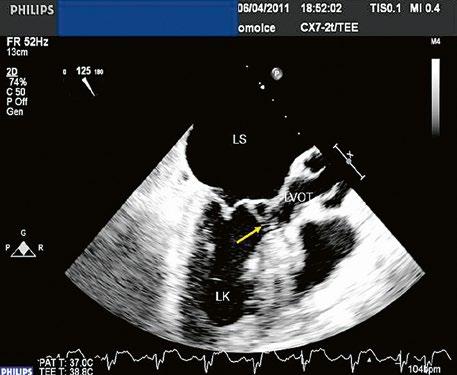

Obr. 45.17 TEE – abnormální úpony mitrální chlopně (označené šipkou) u inkompletního AVSD napříč úzkým výtokovým traktem levé komory (LVOT), přispívají k subvalvární aortální stenóze LK – levá komora, LS – levá síň